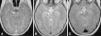

During hospitalisation, she experienced palsy of the VI cranial nerves with ongoing fluctuations in the level of consciousness, leading to performance of a head CT scan with contrast that showed no abnormalities. Forty-eight hours later, the patient underwent a cranial MRI scan that showed a hyperintense T2 signal at the level of the brainstem, centred at the midbrain and extending towards the cerebral peduncles and the pons, with leptomeningeal enhancement and an uptaking punctiform focus at the level of the right cerebellar peduncle (Fig. 1A and B). Given the presence of a brain lesion probably caused by inflammation, the patient was screened for autoimmune diseases, and the antinuclear antibodies, complement and antineutrophil cytoplasmic antibodies tests were all negative. The patient underwent genetic testing for hereditary autoinflammatory diseases (familial Mediterranean fever, periodic fever syndrome due to mevalonate kinase deficiency, TRAPS, BLAU syndrome/early-onset sarcoidosis) that found no mutation associated with her disease. The test for HLA-B51 was negative.

The patient responded well to the treatment, with a gradual improvement of symptoms that allowed the progressive tapering and eventual discontinuation of corticosteroids. The followup MRI at six months after initiation of treatment did not show any pathological changes (Fig. 1C). At present, the patient continues treatment with azathioprine and colchicine, with good results.

Parenchymal involvement is typically found at the level of the brainstem, appearing as a single inflammatory oedematous lesion that is hyperintense on T2 and iso- to hypointense on T1, associated with meningitis.6